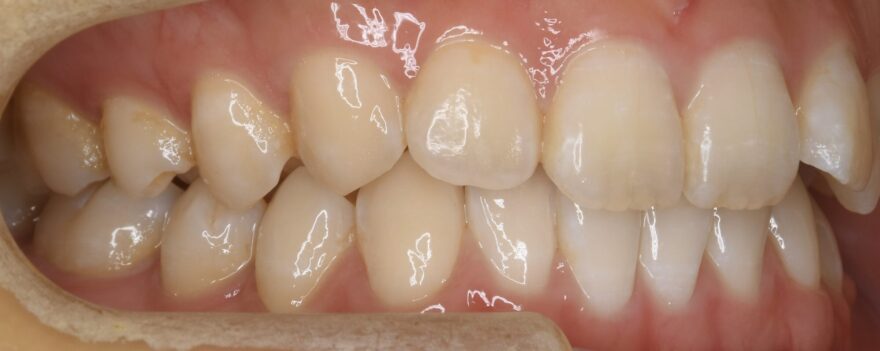

初診時の口腔内写真

上下の歯列の真ん中(正中)が合っていません。

この方向から見ると、前歯が出ていることが分かります。